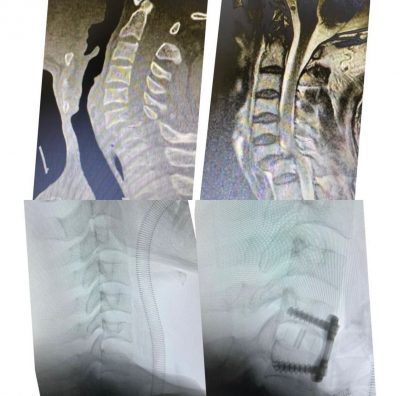

واوضح الفريق الطبي المعالج ان المريض كان قد وصل لطواريء المستشفى بعد اصابته في حادث مروري ادى الى اصابته لخلع كامل للفقرة العنقية السادسة والسابعة مع ضغط كامل للحبل الشوكي مما ادى الى شلل رباعي كامل للاطراف .

وقد قام اطباء العظام المختصين بمستشفى الملك فهد وعلى الفور وفي وقت وجيز من تجهيز المريض لغرفة العمليات بعد ان عمل له اشعة الرنين المغناطيسي والفحوص اللازمة حيث اجريت له عملية جراحية عاجلة لمنع حصول شلل دائم للمريض لا سمح الله .

وقد تم ولله الحمد ارجاع خلع الفقرات العنقية وتحرير الحبل الشوكي وتثبيت الفقرات والمتابعة للمريض بعد نقله للعناية المركزة.